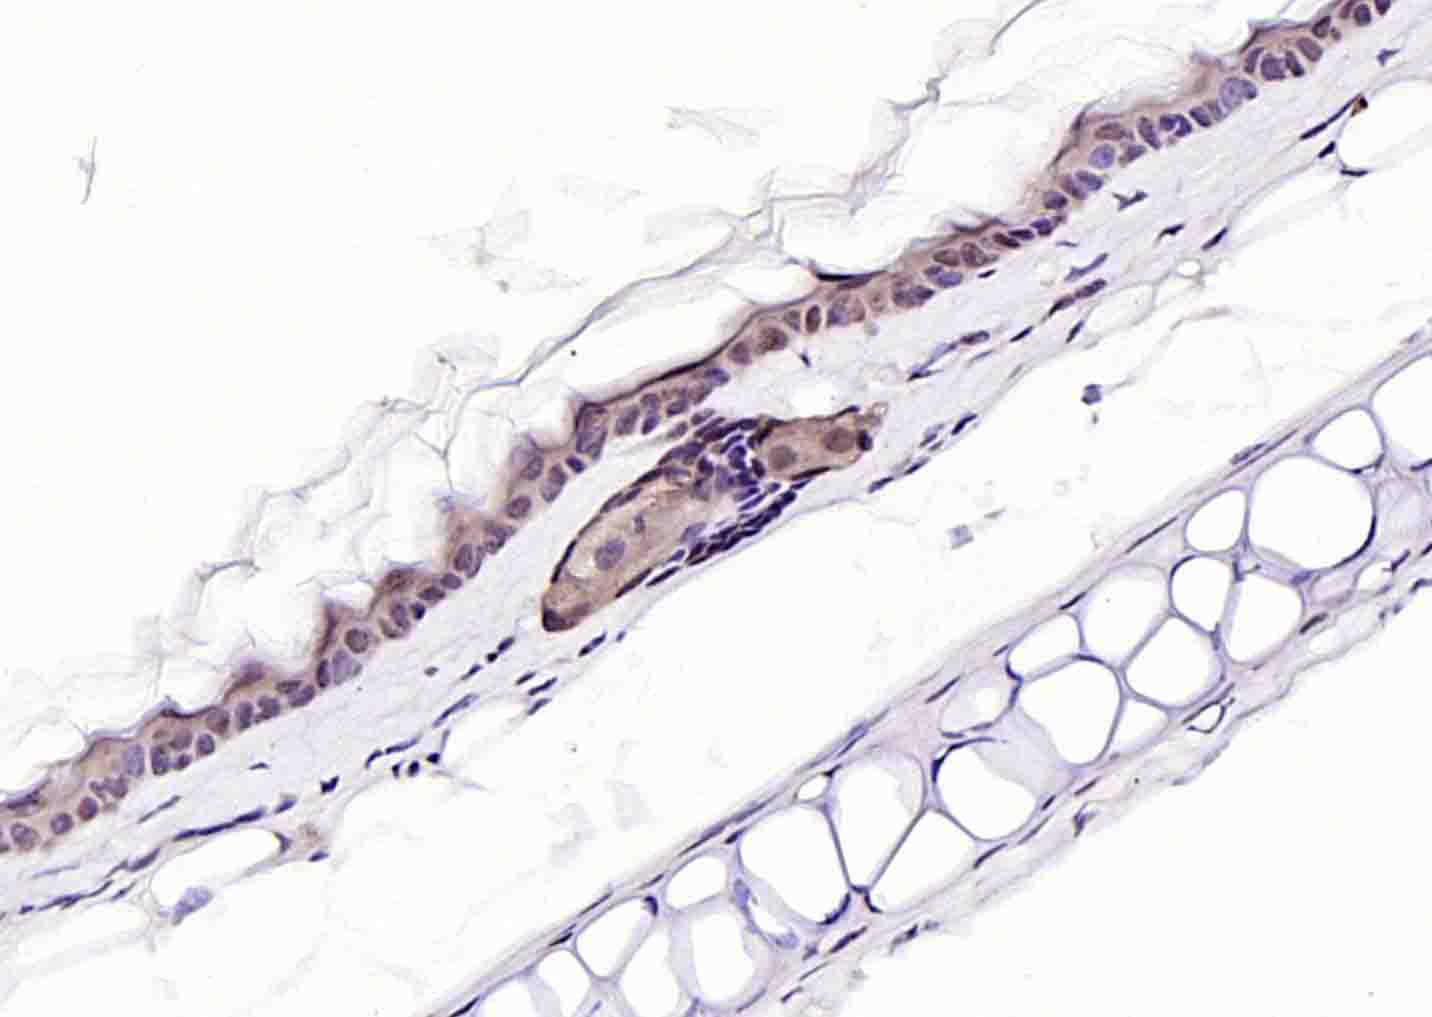

Paraformaldehyde-fixed, paraffin embedded (mouse cerebellum); Antigen retrieval by boiling in sodium citrate buffer (pH6.0) for 15min; Block endogenous peroxidase by 3% hydrogen peroxide for 20 minutes; Blocking buffer (normal goat serum) at 37°C for 30min; Incubation with (PURB) Polyclonal Antibody, Unconjugated (bs-4435R) at 1:200 overnight at 4°C, followed by operating according to SP Kit(Rabbit) (sp-0023) instructionsand DAB staining.

Paraformaldehyde-fixed, paraffin embedded (human stomach); Antigen retrieval by boiling in sodium citrate buffer (pH6.0) for 15min; Block endogenous peroxidase by 3% hydrogen peroxide for 20 minutes; Blocking buffer (normal goat serum) at 37°C for 30min; Incubation with (PURB) Polyclonal Antibody, Unconjugated (bs-4435R) at 1:200 overnight at 4°C, followed by operating according to SP Kit(Rabbit) (sp-0023) instructionsand DAB staining.

Paraformaldehyde-fixed, paraffin embedded (mouse placenta); Antigen retrieval by boiling in sodium citrate buffer (pH6.0) for 15min; Block endogenous peroxidase by 3% hydrogen peroxide for 20 minutes; Blocking buffer (normal goat serum) at 37°C for 30min; Incubation with (PURB) Polyclonal Antibody, Unconjugated (bs-4435R) at 1:200 overnight at 4°C, followed by operating according to SP Kit(Rabbit) (sp-0023) instructionsand DAB staining.

Paraformaldehyde-fixed, paraffin embedded (human placenta); Antigen retrieval by boiling in sodium citrate buffer (pH6.0) for 15min; Block endogenous peroxidase by 3% hydrogen peroxide for 20 minutes; Blocking buffer (normal goat serum) at 37°C for 30min; Incubation with (PURB) Polyclonal Antibody, Unconjugated (bs-4435R) at 1:200 overnight at 4°C, followed by operating according to SP Kit(Rabbit) (sp-0023) instructionsand DAB staining.

Paraformaldehyde-fixed, paraffin embedded (rat placenta); Antigen retrieval by boiling in sodium citrate buffer (pH6.0) for 15min; Block endogenous peroxidase by 3% hydrogen peroxide for 20 minutes; Blocking buffer (normal goat serum) at 37°C for 30min; Incubation with (PURB) Polyclonal Antibody, Unconjugated (bs-4435R) at 1:200 overnight at 4°C, followed by operating according to SP Kit(Rabbit) (sp-0023) instructionsand DAB staining.

Paraformaldehyde-fixed, paraffin embedded (rat skin); Antigen retrieval by boiling in sodium citrate buffer (pH6.0) for 15min; Block endogenous peroxidase by 3% hydrogen peroxide for 20 minutes; Blocking buffer (normal goat serum) at 37°C for 30min; Incubation with (PURB) Polyclonal Antibody, Unconjugated (bs-4435R) at 1:200 overnight at 4°C, followed by operating according to SP Kit(Rabbit) (sp-0023) instructionsand DAB staining.

Paraformaldehyde-fixed, paraffin embedded (mouse skin); Antigen retrieval by boiling in sodium citrate buffer (pH6.0) for 15min; Block endogenous peroxidase by 3% hydrogen peroxide for 20 minutes; Blocking buffer (normal goat serum) at 37°C for 30min; Incubation with (PURB) Polyclonal Antibody, Unconjugated (bs-4435R) at 1:200 overnight at 4°C, followed by operating according to SP Kit(Rabbit) (sp-0023) instructionsand DAB staining.

Paraformaldehyde-fixed, paraffin embedded (Rat heart); Antigen retrieval by boiling in sodium citrate buffer (pH6.0) for 15min; Block endogenous peroxidase by 3% hydrogen peroxide for 20 minutes; Blocking buffer (normal goat serum) at 37°C for 30min; Antibody incubation with (PURB) Polyclonal Antibody, Unconjugated (bs-4435R) at 1:400 overnight at 4°C, followed by operating according to SP Kit(Rabbit) (sp-0023) instructions and DAB staining.